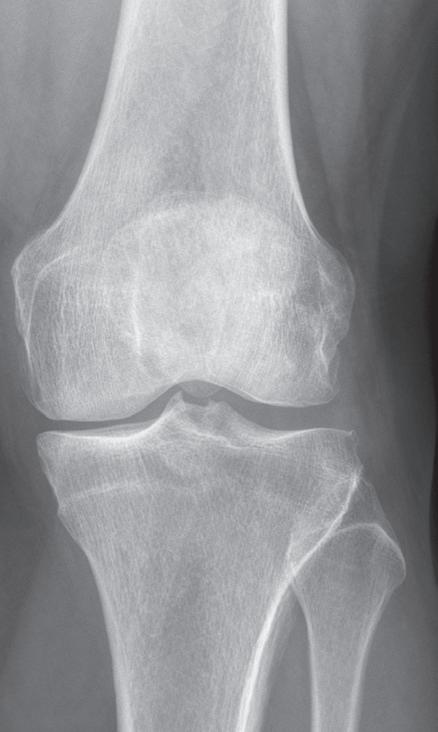

kloubu nebo jako startovací bolest na začátku pohybu. Později se přidává i bolest klidová a noční. Původní krátká ranní ztuhlost přechází ve zhoršování funkce a dochází k postupnému omezení rozsahu hybnosti v kloubu. Objektivně nacházíme defiguraci kloubu na podkladě tvorby artrotických osteofytů. Objevuje se typická deformita ve smyslu varozity nebo valgozity (genu varum, genu valgum, obr. 19.2, obr. 19.3), v těžších případech doprovázená různým stupněm flekční kontraktury (genu flectum). Typicky jsou přítomné drásoty (krepitus) při pohybu kloubu, palpační bolestivost, v období dekompenzace i známky reaktivní synovialitidy či výpotku. Dochází k laxitě –insuficienci vazivového aparátu na konvexitě deformity, a naopak jeho retrakci na konkavitě. Zjišťujeme omezení rozsahu pohybu různého stupně, v pozdním stadiu může přejít až v semiankylózu, nebo dokonce ankylózu, prakticky vždy ve funkčně nevýhodném postavení.

Základem diagnózy je klinické vyšetření doplněné o rentgenový snímek obvykle ve dvou projekcích

Obr. 19.2: Varózní deformita pravého kolenního kloubu (levé koleno již po korekci osy v rámci implantace náhrady kolenního kloubu) – (a) a rentgenový nález úhlové deformity s nálezem pokročilých artrotických změn (b)

(předozadní a bočná). Na rentgenovém snímku se gonartróza zpočátku projevuje přihrocením interkondylické eminence a subchondrální sklerózou v místě přetížení, později zúžením, případně až zánikem kloubní štěrbiny, vznikem osteofytů, pseudocyst a případnou úhlovou deformitou. Dle nálezu rovněž klasifikujeme stupeň gonartrózy podle Kellgrena-Lawrence (viz kap. 17, obr. 19.4), což má praktický význam v indikaci farmakoterapie i balneoterapie.